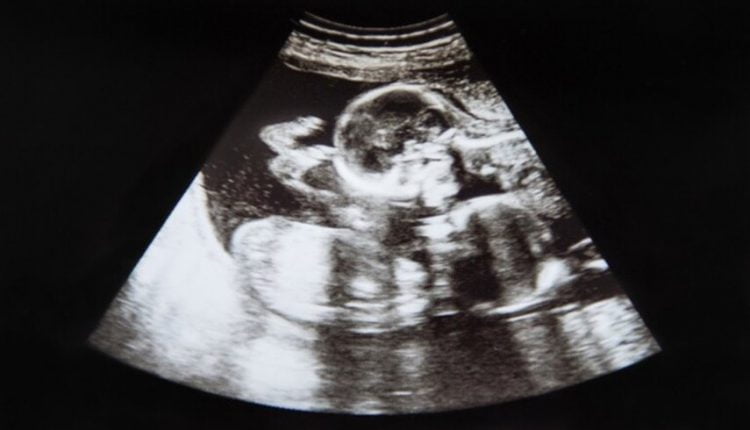

اختفى جنين طفلة في رحم أمها، لكنها تركت لشقيقها التوأم، علامة تشبه صورتها الخاصة على جسمه.

ولدى بايلون غيفنز علامة مميزة على ركبته على شكل حبة “الكاجو”، على غرار شكل شقيقته التوأم، عندما تم فحصهما في الرحم في الأسبوع العاشر من الحمل.

ولم يستطع الأطباء العثور على نبضات قلبها بعد 11 أسبوعا من الحمل، ما أثار مخاوف من نموها بوتيرة أبطأ من شقيقها بايلون.

ووصف الأطباء هذه الحالة باسم “متلازمة التوأم المتلاشي”، وهي ظاهرة يختفي فيها جنين أو أكثر في حالة الحمل بتوائم، ويحدث للجنين إجهاض تلقائي، لكنه يمتص بواسطة الجنين الآخر أو الأم أو المشيمة.